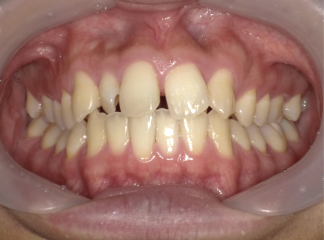

Before Photo

Before

After Photo

After

主訴

上の前歯の隙間が気になる。

治療期間

2年1か月

料金

相談料0円、検査料33,000円、動的矯正治療費990,000円、保定装置料5,500円x2枚(必要枚数)

治療概要

上の前歯に隙間があるため、前歯を後退させながら、隙間を閉じた。

この時、上下の前歯が強く干渉すると再度隙間が空いてくるため、上下前歯の咬合が強くならないように配列した。

矯正での歯の移動のリスクとして歯根吸収、歯肉退縮、歯髄怪死が考えられます。

保定装置の装置を怠ると隙間が生じてくる可能性があります。